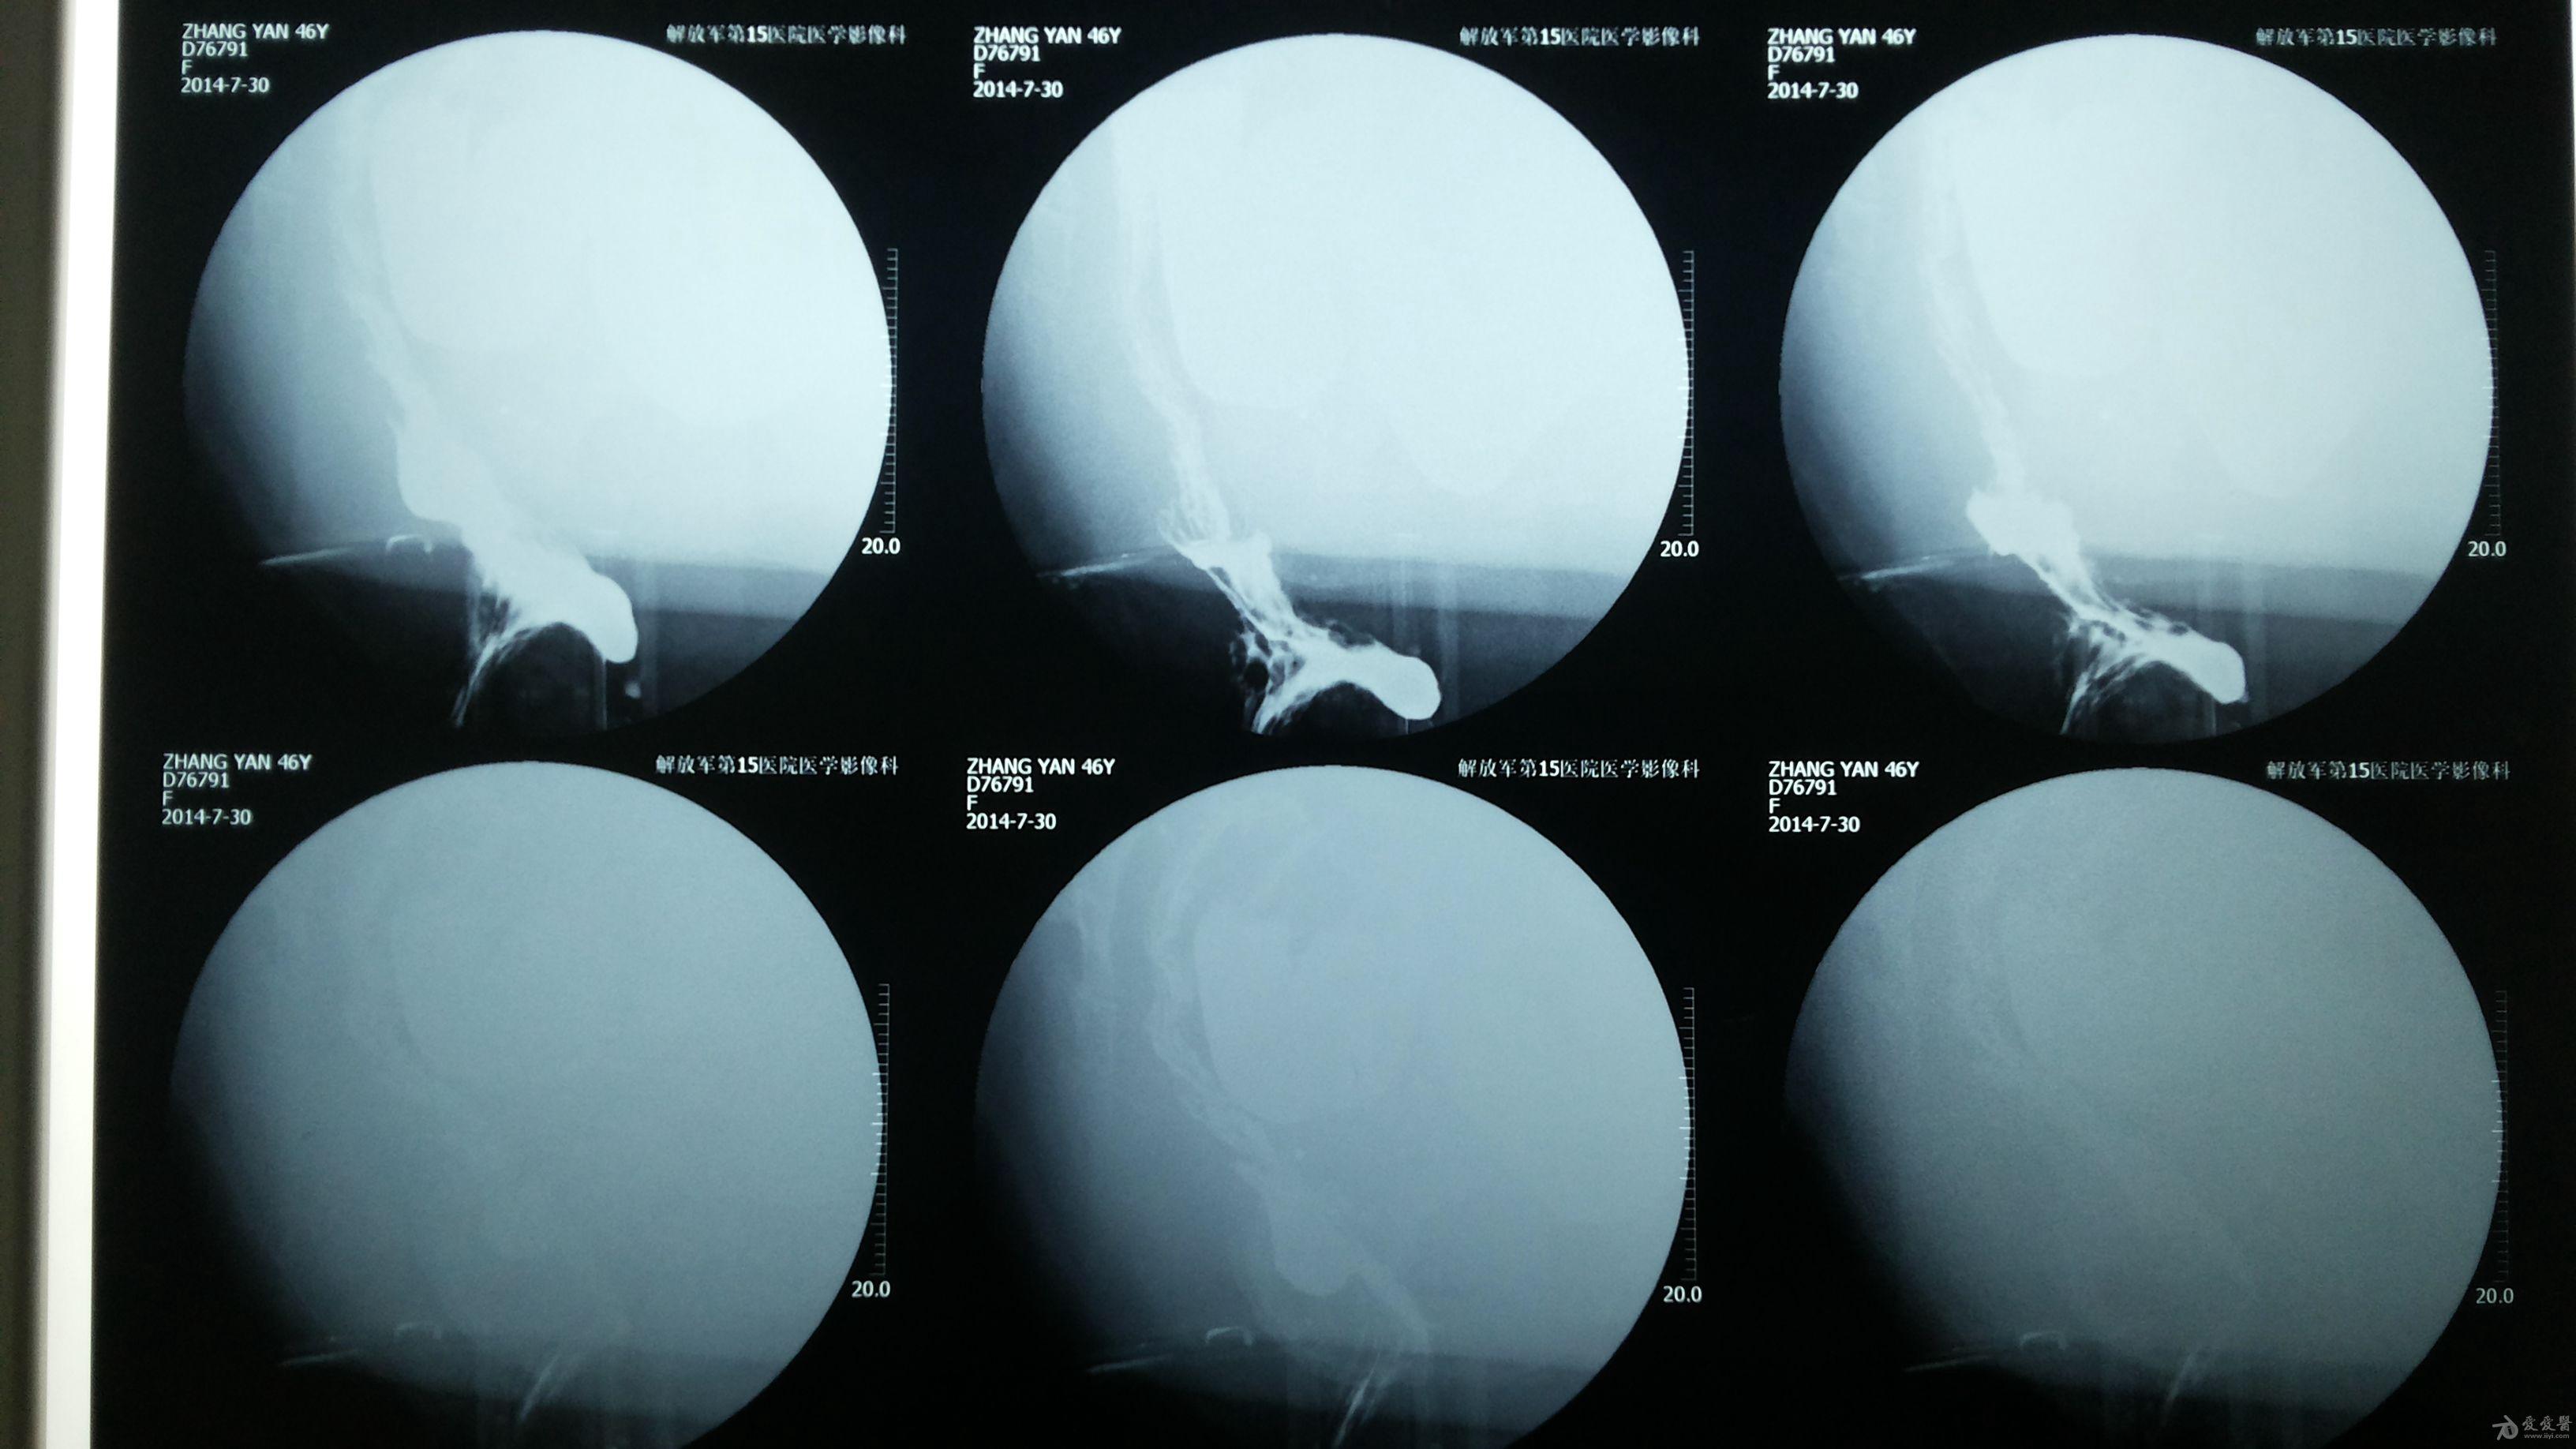

直肠前突的片子病人便秘请教处理方法

图片尺寸3264x1836